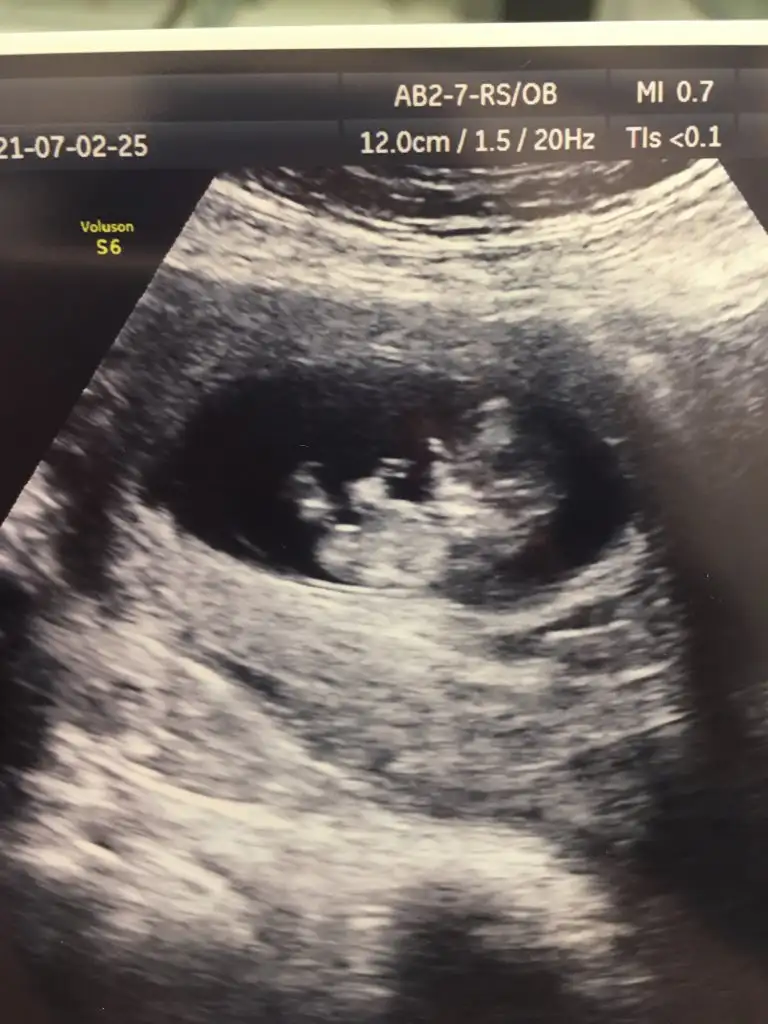

Bugün 10+2 yim kanama alanlarım var ama çok küçükmüş doktor birşey olacağını sanmıyorum dedi progestan hapa devam ediyorum bu görüntüde hala bebeğimi ayırt edemiyorum başı hangi tarafta ayakları nerde görebilen var mı

Başı solda canım, mersinde mi yaşıyorsun?